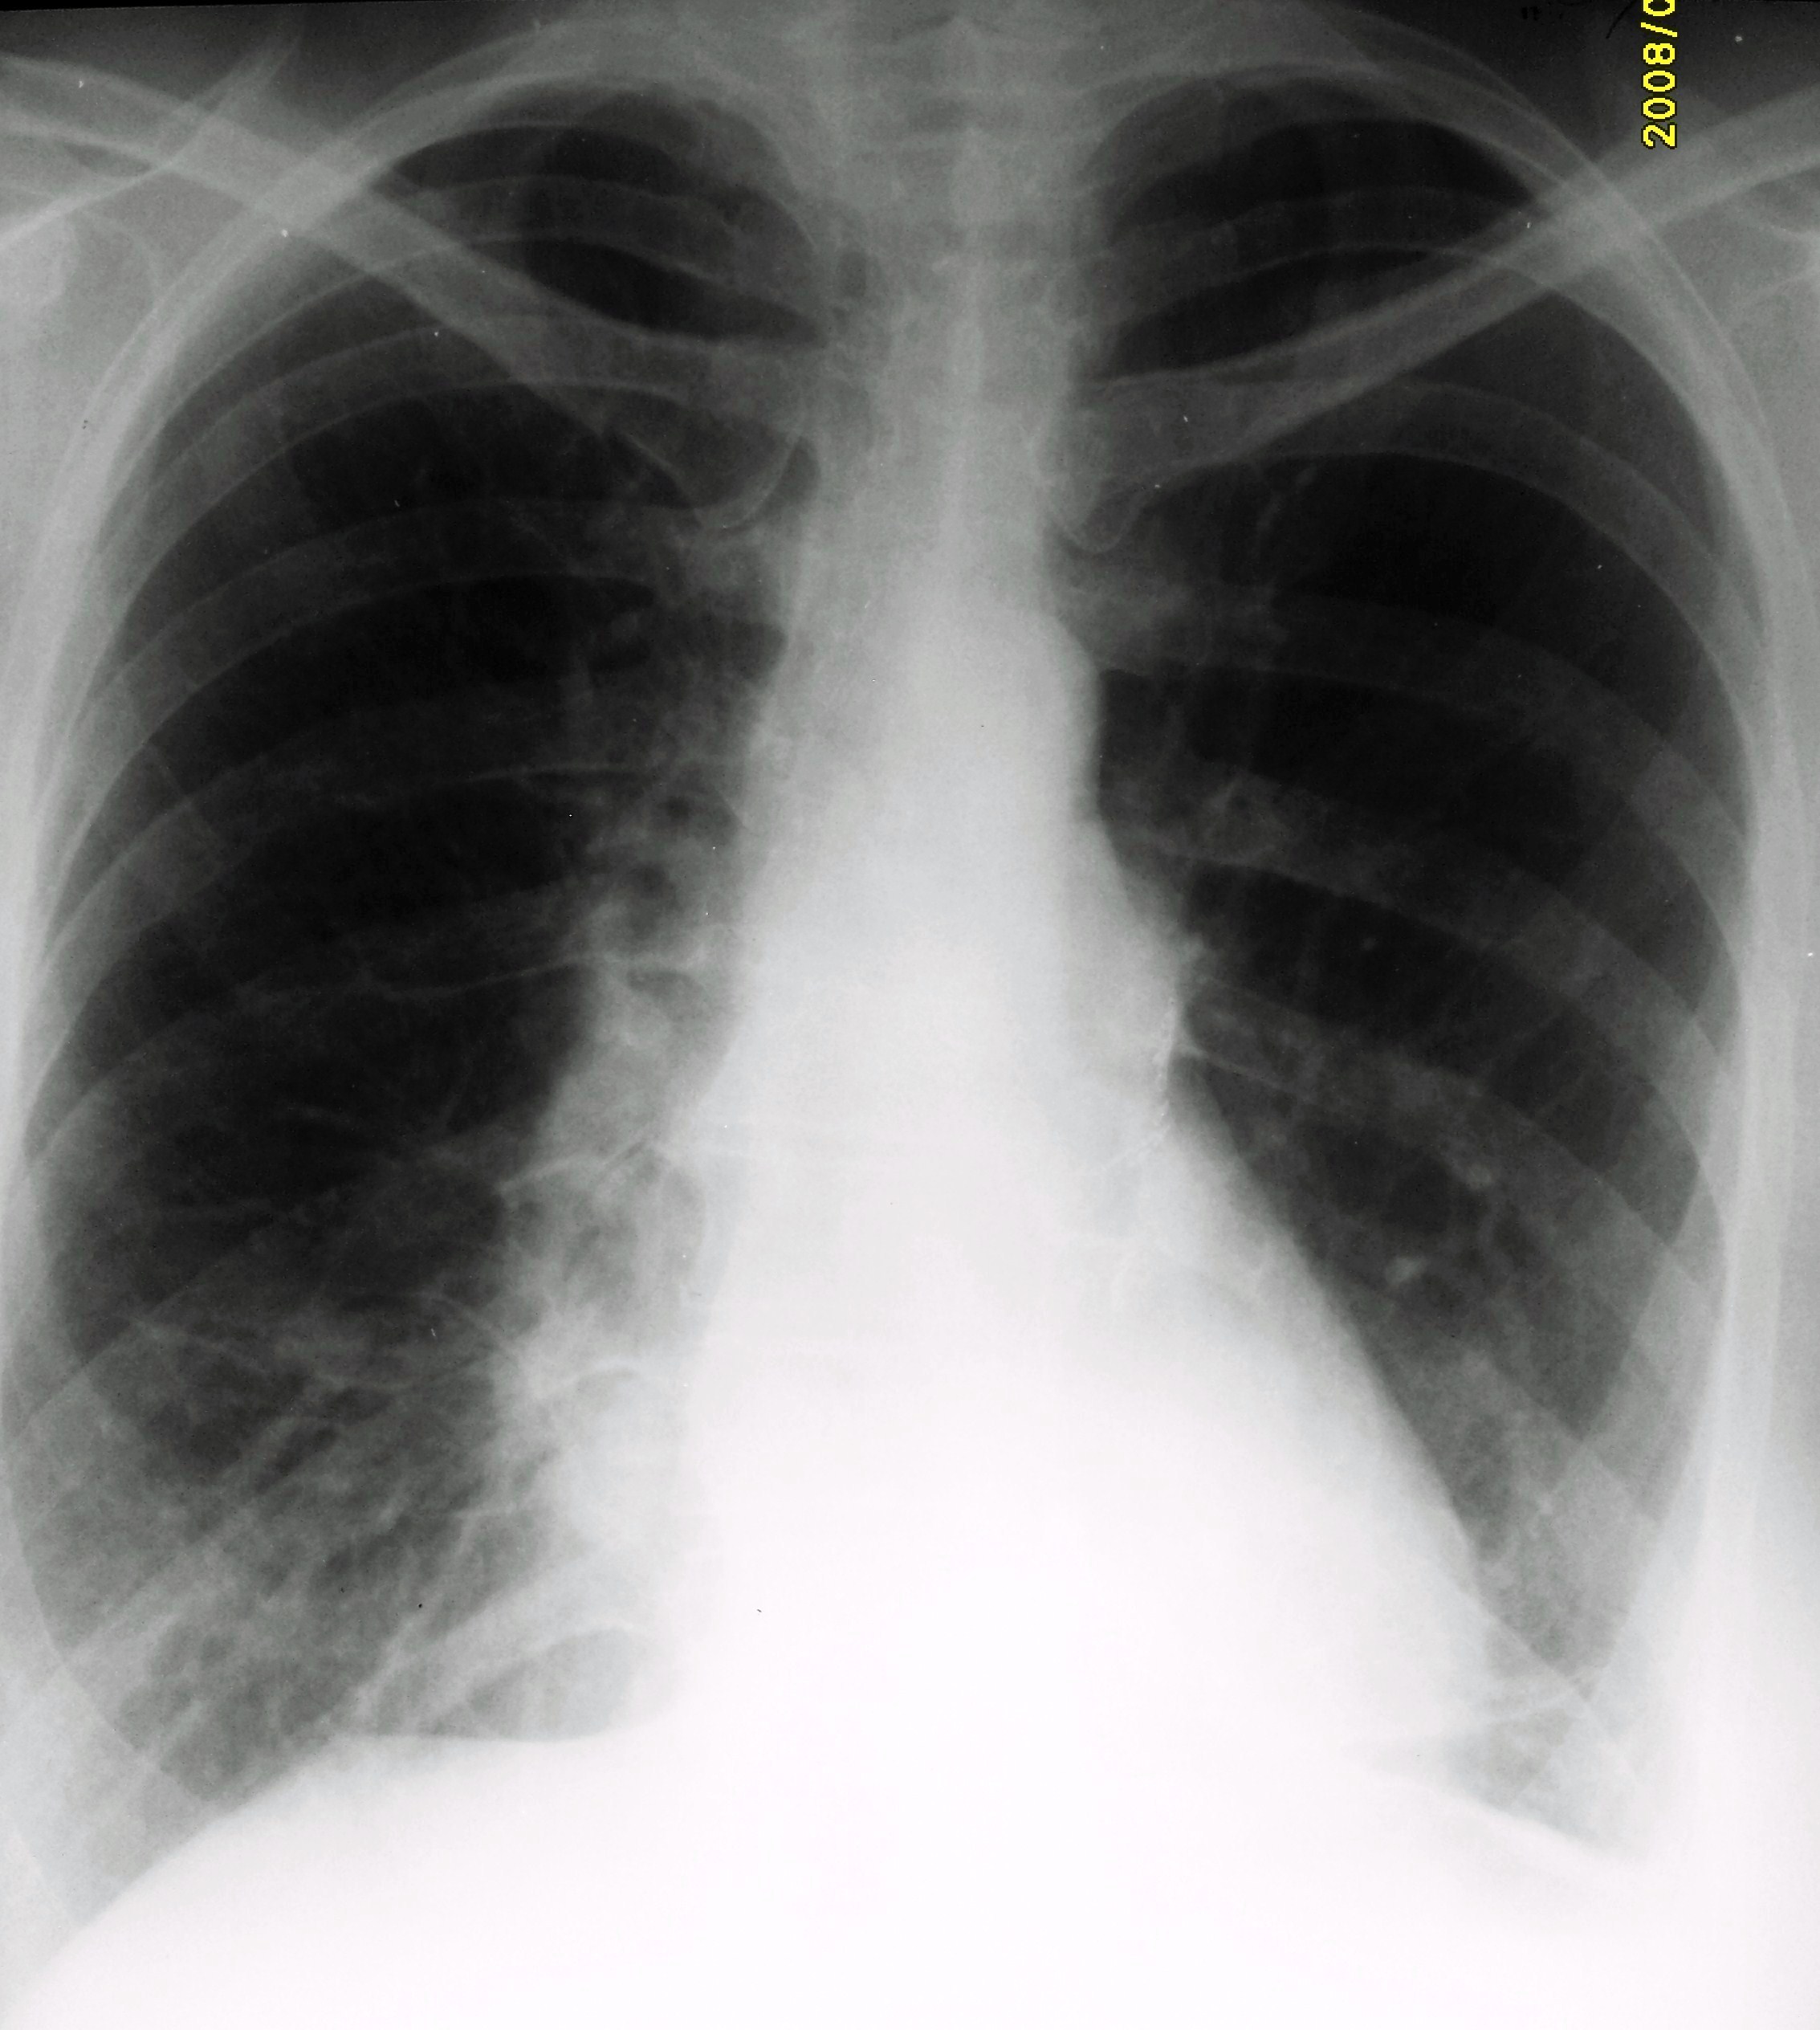

Снимок легких при туберкулезе является важным методом диагностики этого заболевания. На рентгеновских снимках можно увидеть изменения в легких, которые свойственны туберкулезу.

Нормальная рентгенограмма ОГК

Фотографии снимков легких при туберкулезе

В данной статье представлены многочисленные фотографии снимков легких при туберкулезе, чтобы помочь вам понять, как выглядят изменения легких на рентгеновских снимках при этом заболевании.